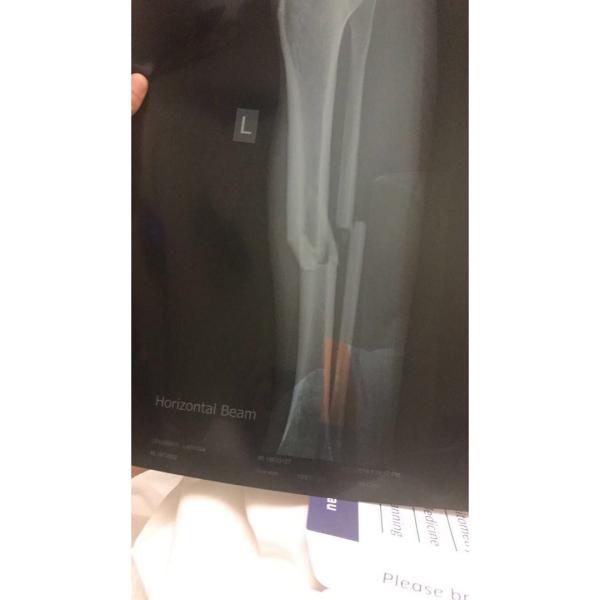

Devastatingly for Crummer, in that moment, everything was not okay. The collision had resulted in breaks in the tibia and fibula bones in her left leg.

“The surgeon said that the break I had was equivalent to a break in a motorcycle accident.”

Almost immediately Crummer was in surgery to insert a rod into the shattered bones. While for most people this would be the start of the healing process, unfortunately for the 24-year-old it would begin a 14 month process she describes as a “nightmare”.

“I was told it was nine to 12 months, but then I had all these complications. I got Compartment Syndrome when they were putting the rod in during the first surgery.”

“The surgeon said if they don’t catch it within 24 hours you can actually lose your leg. So I went under [anesthesia] thinking I was just getting a rod put in my leg and woke up with cuts on both sides of my leg.”